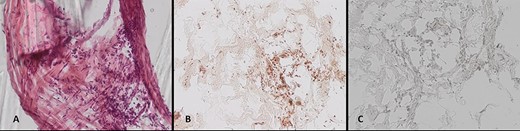

Pieces of the infiltrated cranioplasty were microscopically examined after topical staining as described above. Immunohistology clearly identified meningioma cell formations inside the cranioplasty (Fig. 3B and C), and topographical microscopy showed meningioma formations along the preformed caverns (Fig. 3A).

(A–C) Histological work-up of the explanted cranioplasty: (A) hematoxylin/eosin staining, immunohistochemical staining for (B) epithelial membrane antigen, and (C) GFAP (all ×20 magnification).